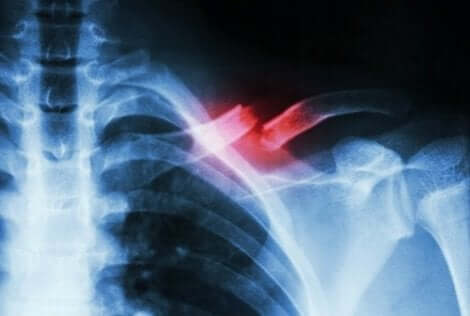

Stressfrakturer inträffar när en liten spricka i benet uppstår av något annat än ett starkt slag. Vanligtvis utlöses tillståndet av repetitiva rörelser eller en snabb ökning av intensitet hos en aktivitet.

Dessa typer av frakturer är inte enkla att diagnostisera. Därför kräver de en medicinsk expert och kompletterande tester för att särskilja dem från andra tillstånd. Detta eftersom frakturen ofta inte syns på röntgen.

När det inte finns någon kontinuitet i benvävnaden är det för att det finns en fraktur. De flesta av dessa skador inträffar på grund av slag eller trauma. Men i fallet stressfrakturer är orsaken ofta svaghet eller utmattning.

En stressfraktur är en form av spricka i benet som inträffar på grund av mikrotrauma eller överbelastning. De kan leda till allvarlig smärta när man utför vissa fysiska aktiviter, men försvinna när man är klar.